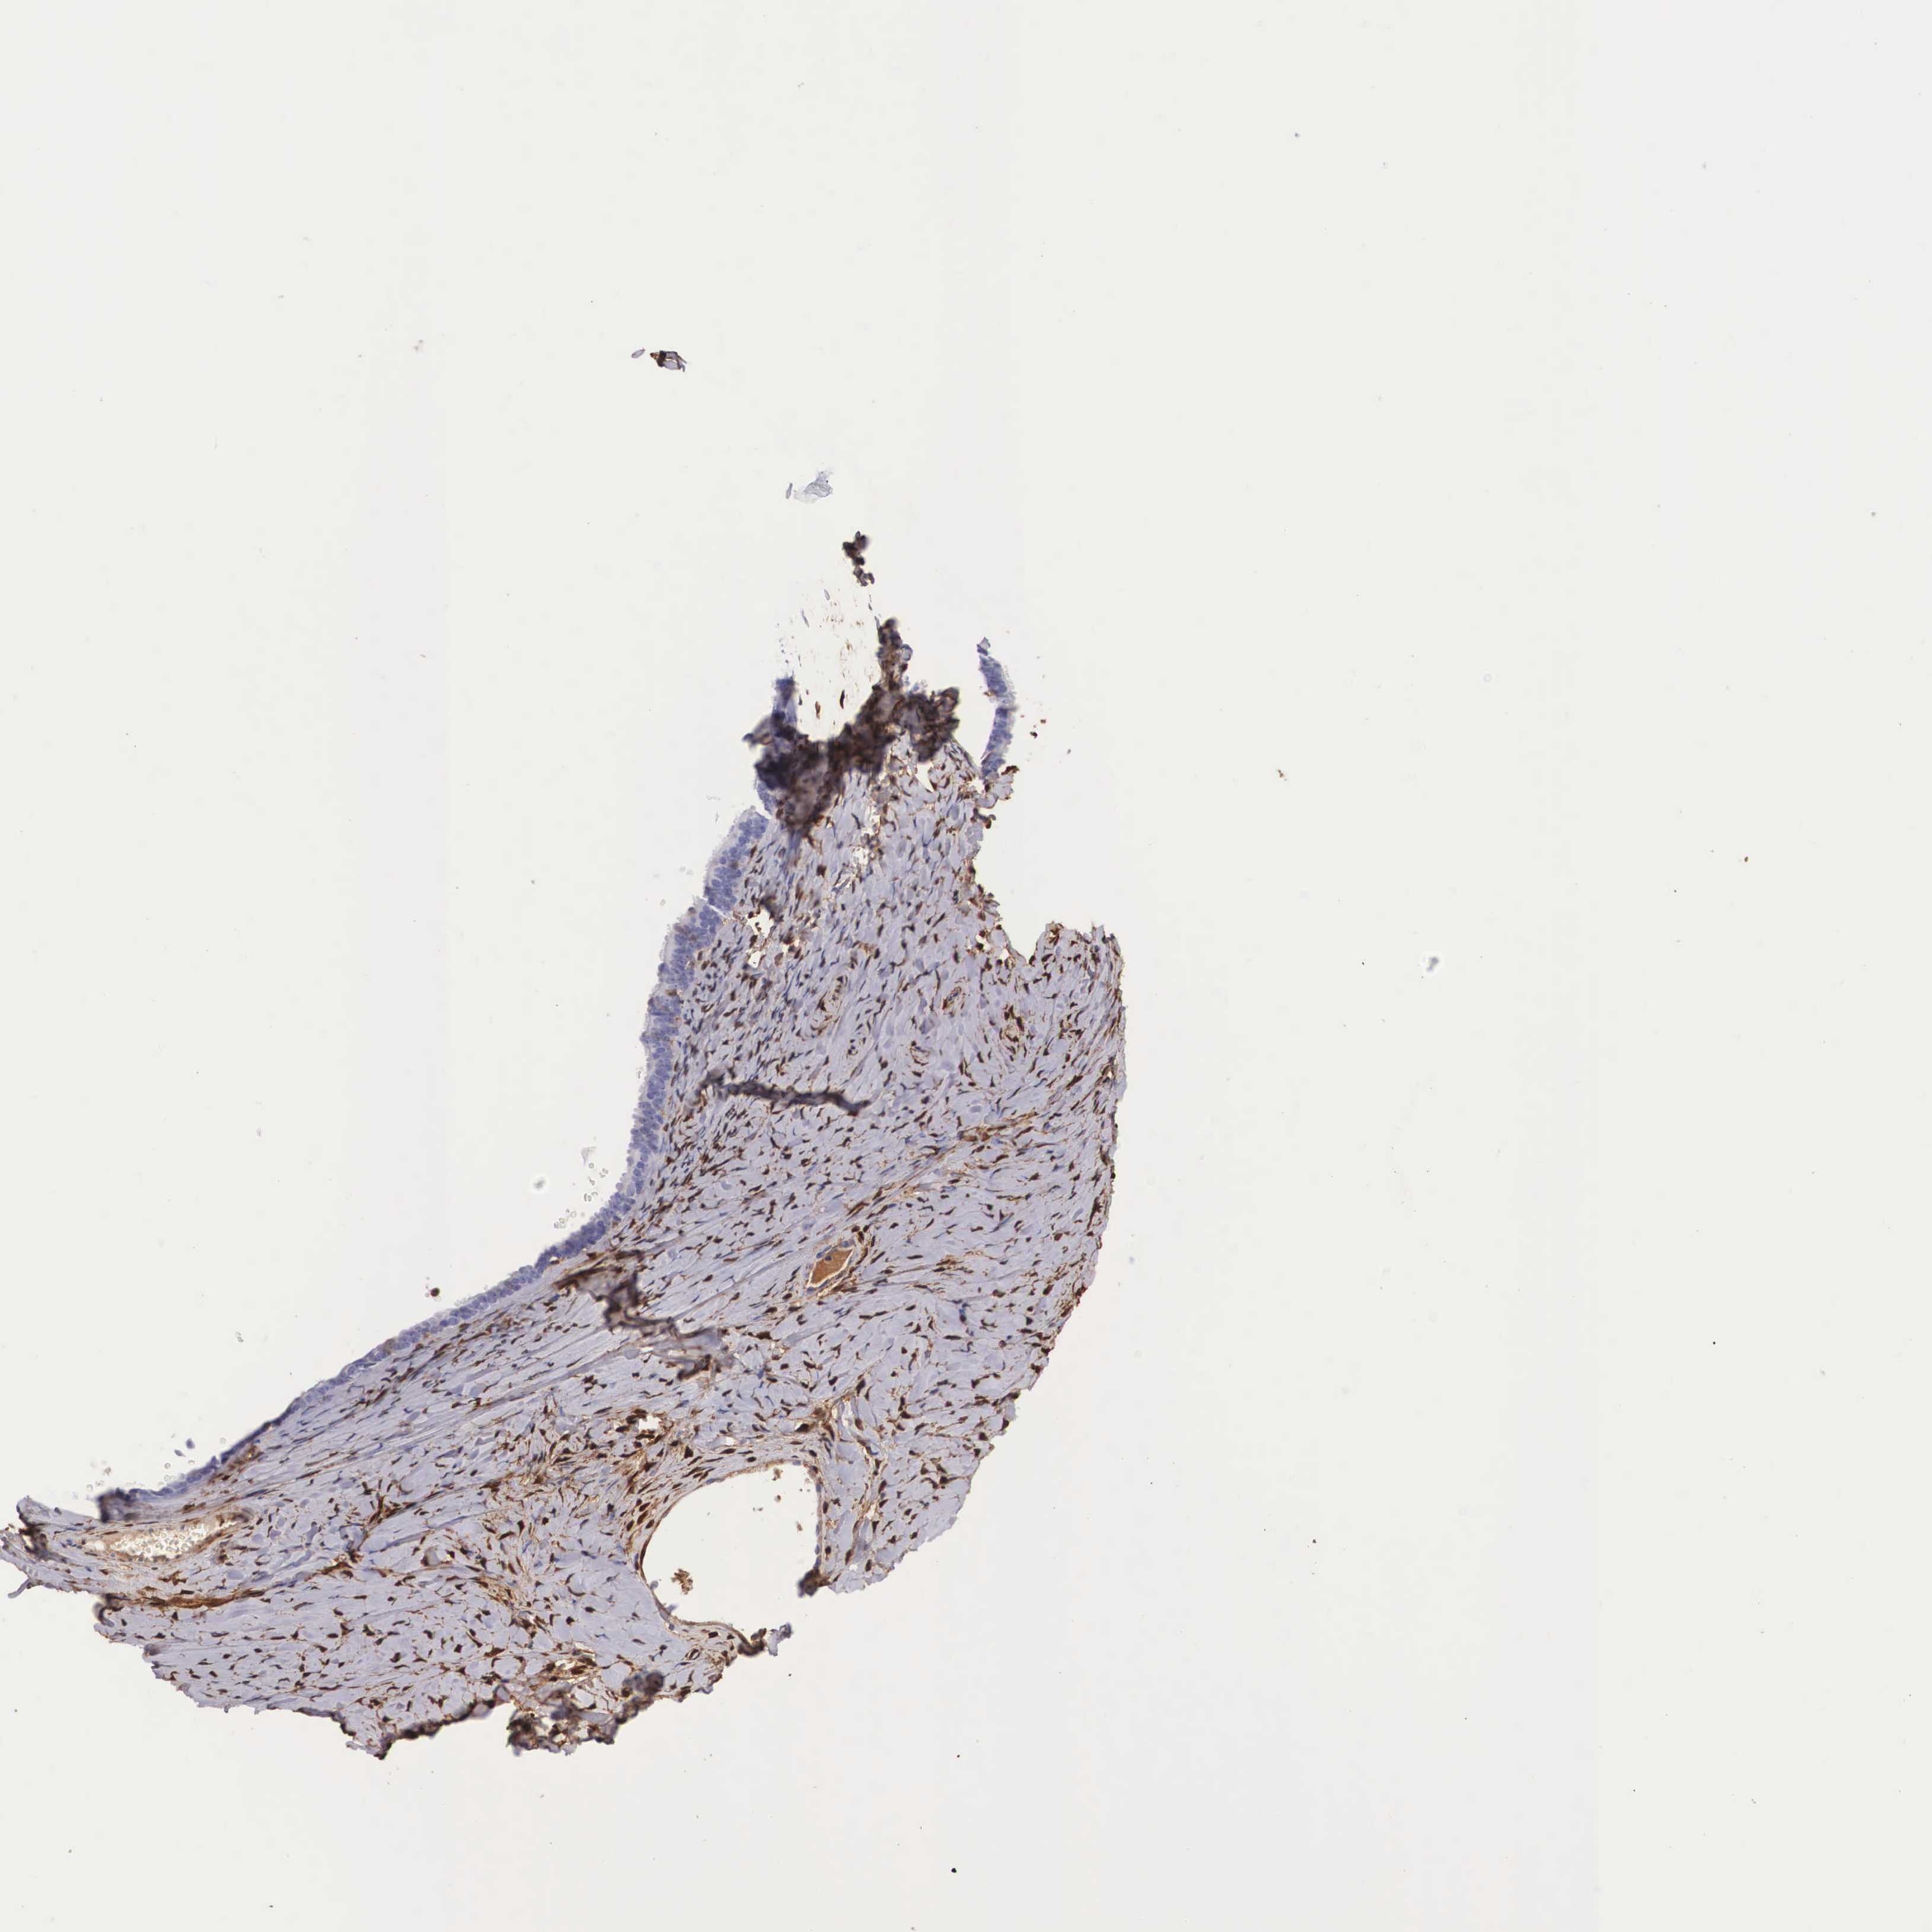

OVARIAN CANCER - Protein expressioni

A mouse-over function shows sample information and annotation data. Click on an image to view it in a full screen mode. Samples can be filtered based on level of antibody staining by selecting one or several of the following categories: high, medium, low and not detected. The assay and annotation is described here.

Note that samples used for immunohistochemistry by the Human Protein Atlas do not correspond to samples in the TCGA dataset.

Antibody stainingi

Antibody staining in the annotated cell types in the current human tissue is reported as not detected, low, medium, or high, based on conventional immunohistochemistry profiling in selected tissues. This score is based on the combination of the staining intensity and fraction of stained cells.

Each image is clickable and will lead to virtual microscopy that enables deeper exploration of all samples and also displays staining intensity scores, fraction scores and subcellular localization as well as patient and tissue information for each sample.

Antibody HPA000646

Antibody CAB002157

Staining

High

Medium

Low

Not detected

Intensity

Strong

Moderate

Weak

Negative

Quantity

>75%

75%-25%

<25%

None

Location

Nuclear

Cytoplasmic/membranous

Cytoplasmic/membranous,nuclear

Carcinoma, endometroid

Cystadenocarcinoma, serous, NOS

Cystadenocarcinoma, mucinous, NOS